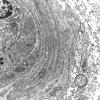

VASCULAR

Hypoxia-Ischemia, fetal-neonatal

White Matter (12)